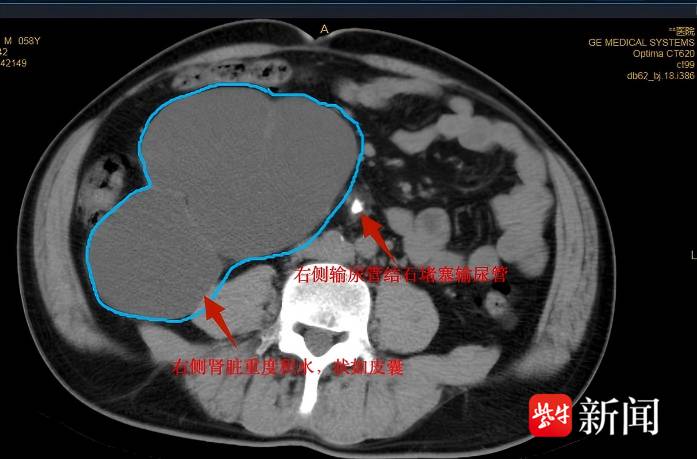

可还没等黄先生缓过劲,更坏的消息来了。医生的语气沉了下来:“您右边输尿管上段还有一颗结石,但这颗更麻烦,它堵了太久,右边的肾已经严重积水,整个肾都变形了,现在几乎没什么功能,成了个‘皮囊肾’,得尽快切。”

带着不安,黄先生和家人找到了南京江北医院泌尿外科。接诊的徐建华副主任医师看完他的检查报告,立刻明白了问题的紧迫性:“左侧结石是‘急症’,先解决它缓解疼痛;右侧坏死的肾是‘隐患’,必须尽快切除,不然可能引发感染、高血压,甚至更严重的问题。”

术中破开右侧皮囊肾,抽吸出约2700ml浑浊囊液